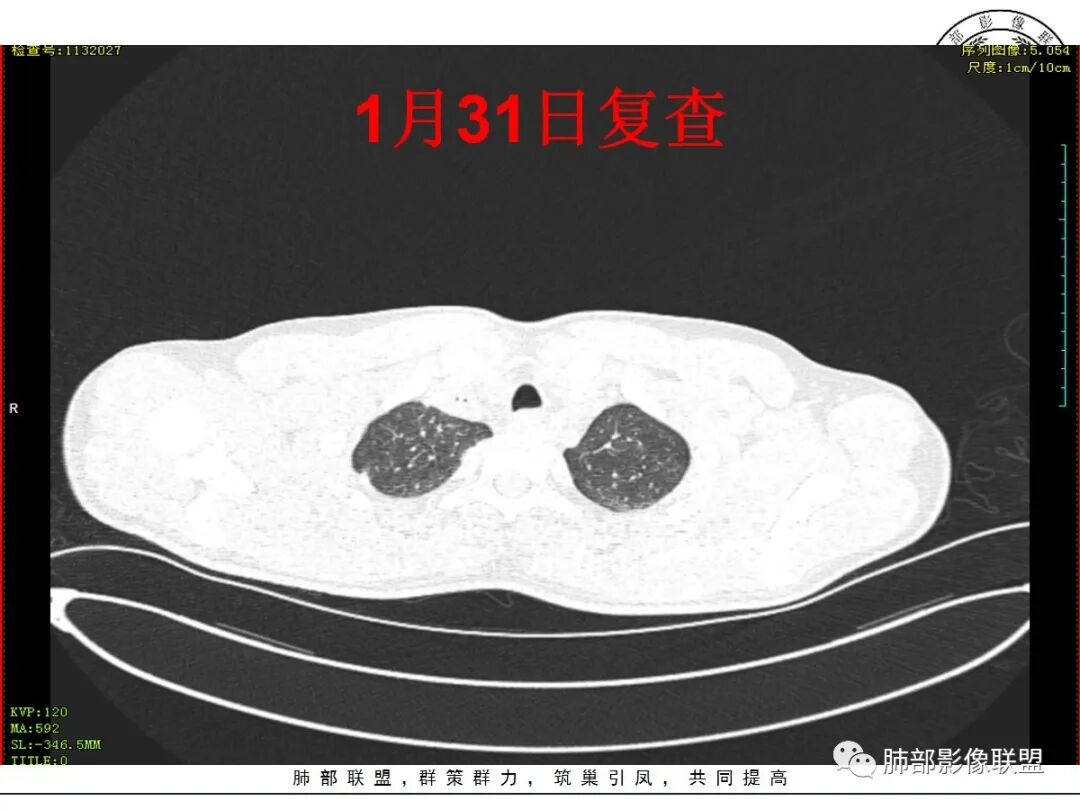

复查及病史